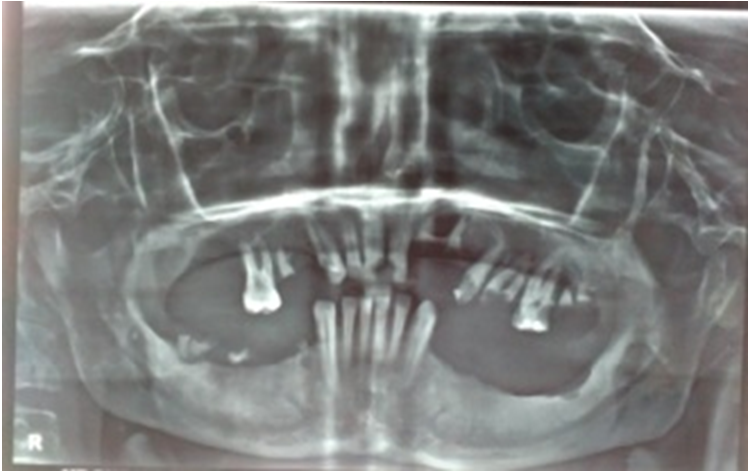

A 44 -year -old male was referred from the dental department to Otorhinolaryngology department with chief complaints of painless, progressive enlargement of gum and small granular lesionsonboth gumswith on and off bleeding episodes over thepast one year. There was no history of dental trauma or any dental surgery. He had been treated several times for this condition, but didn’t notice any improvement. Intra-oral examination revealed small papilliferous masses along both gingiva, in canine and molar regions, and adjacent vestibule. The gingivae were red, irregular, granular in appearance (Figure 1). It was painless to touch, but started bleeding on touch. He had a poor oral hygiene with dental caries. The rest of the ear nose throat examination was normal and there was no cervical lymphadenopathy. Panoramic X-ray (OPG) revealed multiple periapical abscesses (13,21,22,25,27), chronic generalized periodontitis and infected radicular cyst (26) (Figure 2). Blood counts revealed a slight increase in lymphocyte count and elevated erythrocyte sedimentation rate (ESR). A provisional diagnosis of inflammatory gingival enlargement was made andbiopsy under local anesthesia from multiple involvedsiteswas done. Biopsy revealed features consistent with tuberculosis, having many epitheloid cell granulomas with Langhans’ as well as a foreign body type of giant cell reaction and positive ZN staining for acid fast bacilli (Figure 3).

Figure 2 Panoramic X-ray (OPG) revealing multiple periapical abscesses (13,21,22,25,27), chronic generalized periodontitis and infected radicular cyst (26).